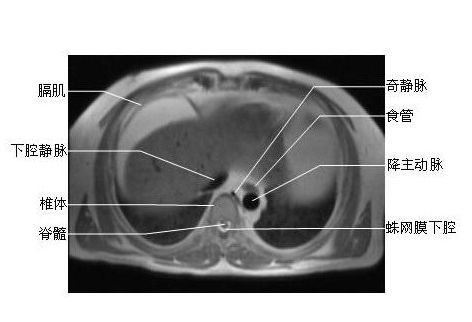

【高清mri图】脊柱磁共振mri解剖

图片尺寸902x526